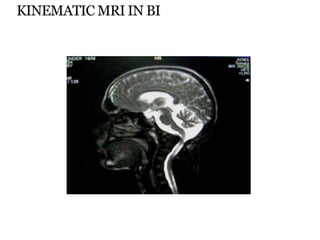

KINEMATIC MRI IN BI